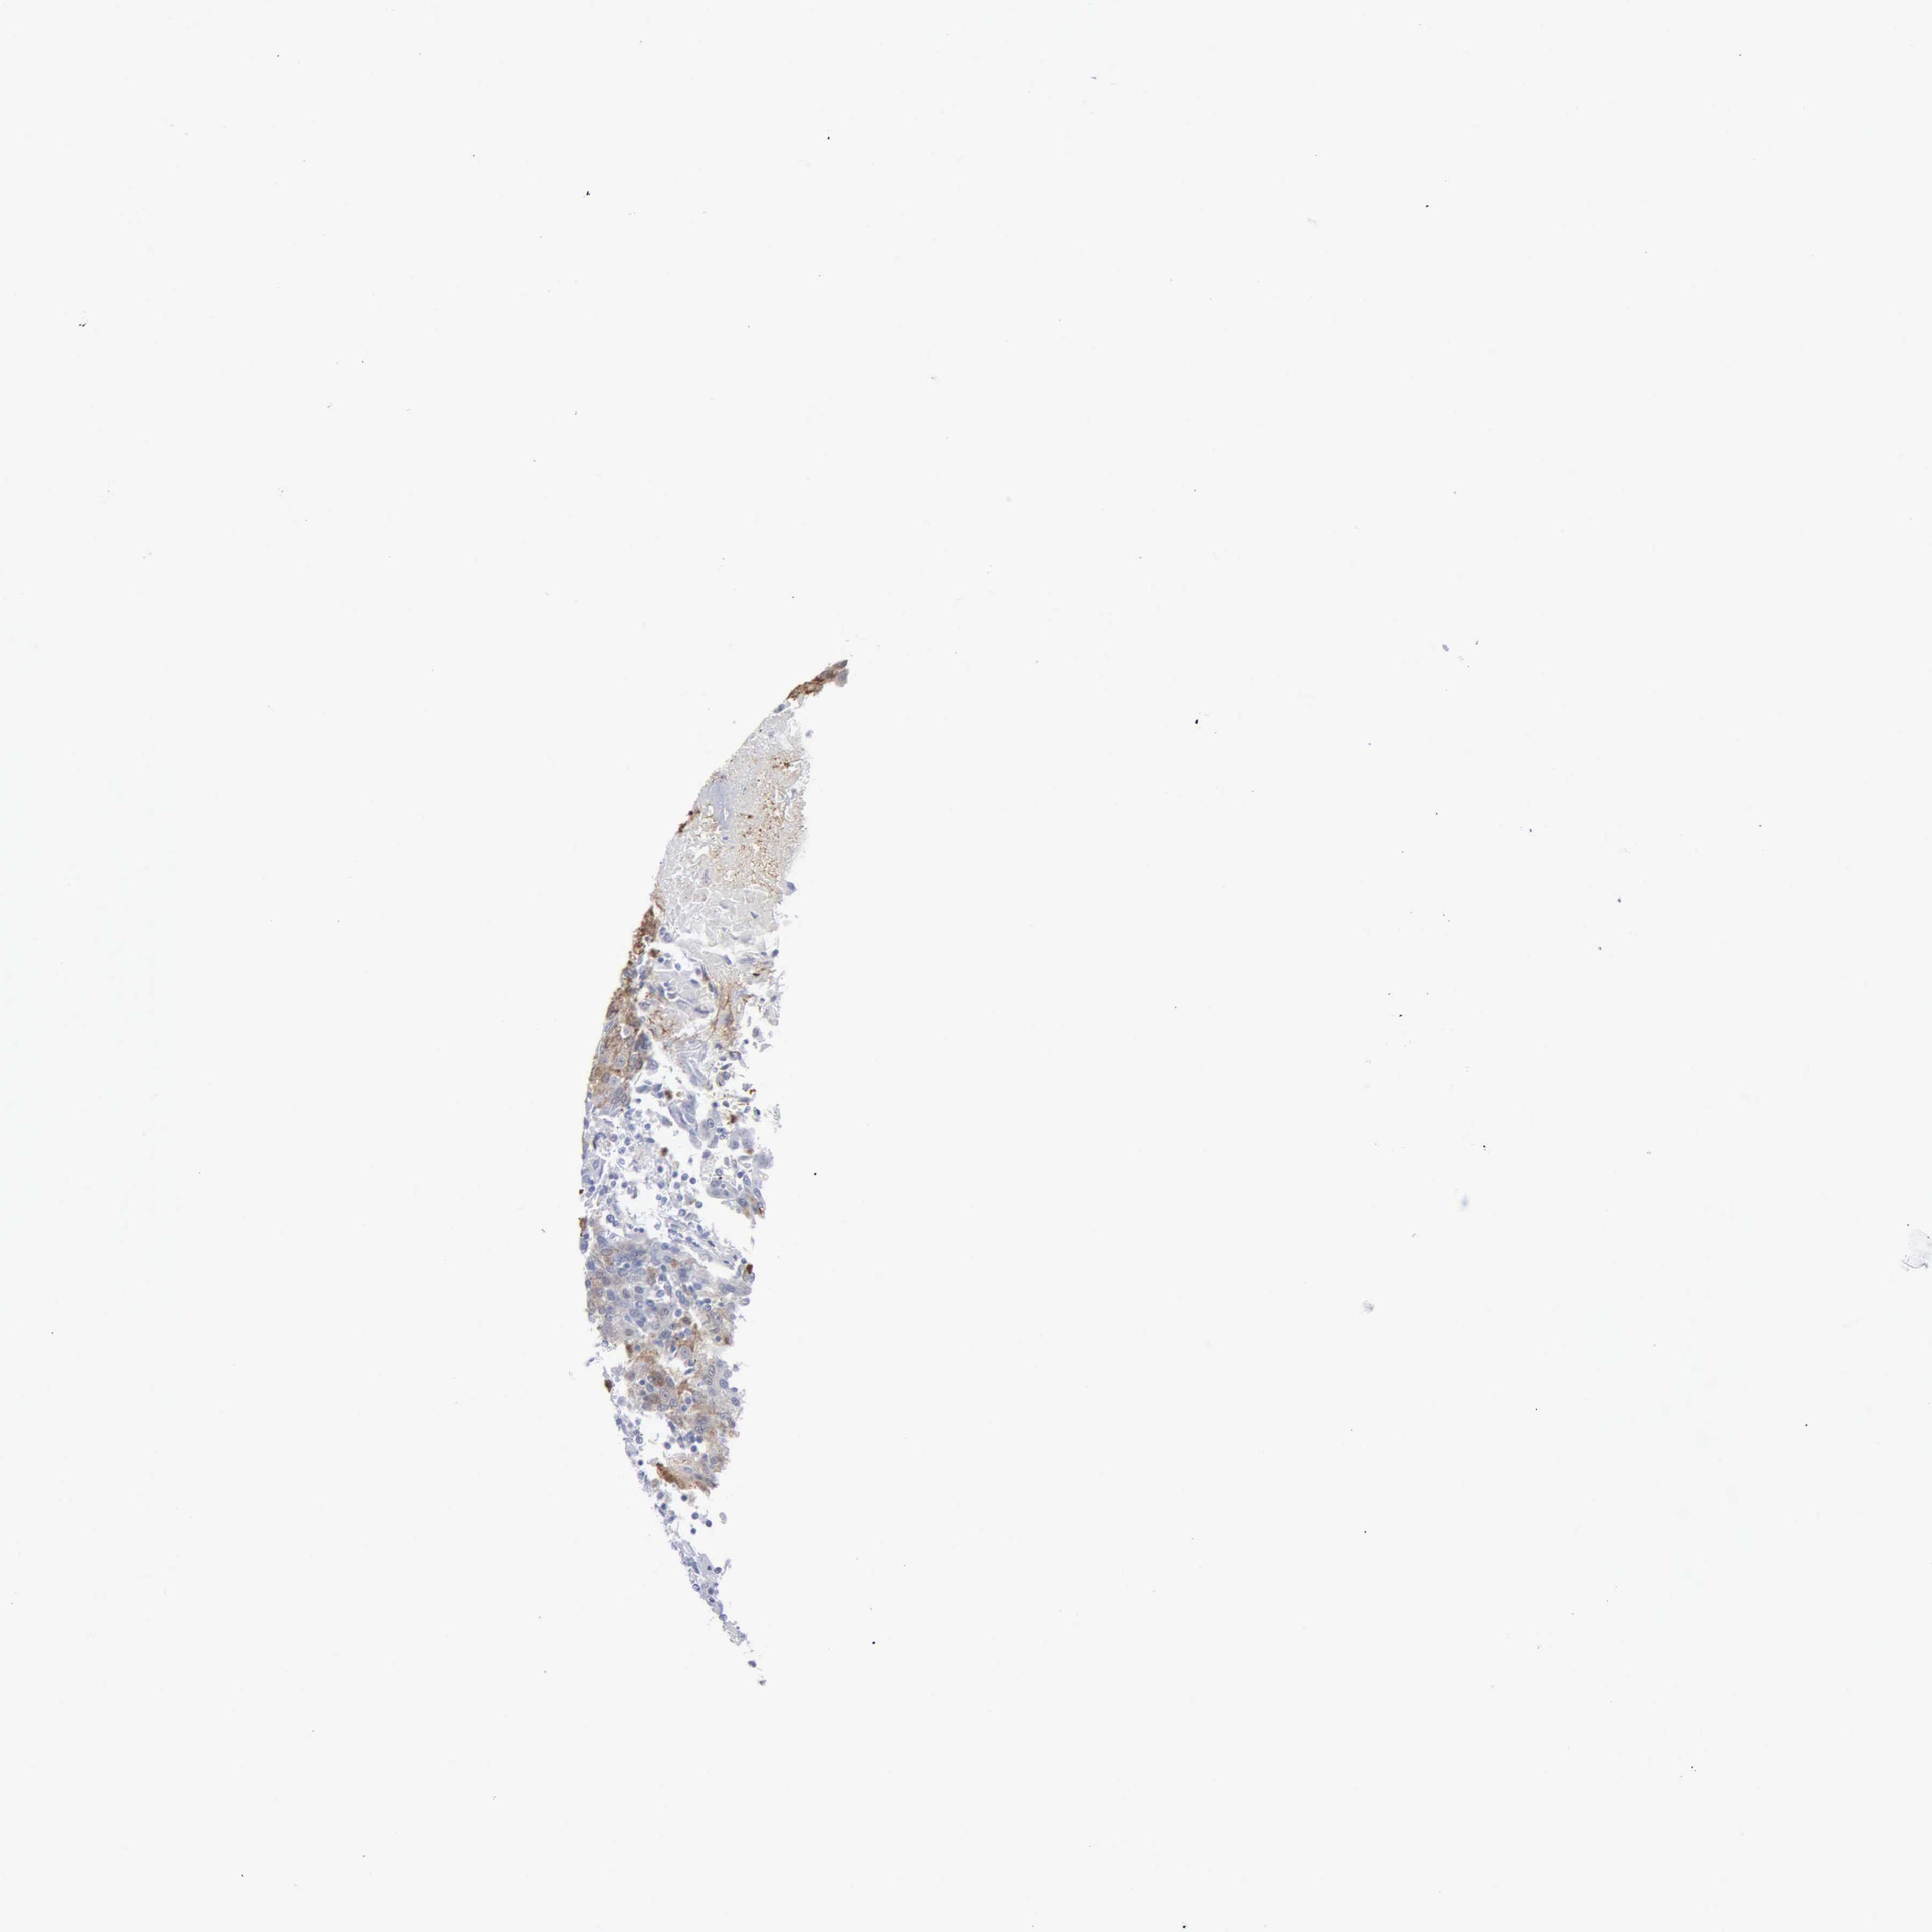

UROTHELIAL CANCER - Protein expressioni

A mouse-over function shows sample information and annotation data. Click on an image to view it in a full screen mode. Samples can be filtered based on level of antibody staining by selecting one or several of the following categories: high, medium, low and not detected. The assay and annotation is described here.

Antibody stainingi

Antibody staining in the annotated cell types in the current human tissue is reported as not detected, low, medium, or high, based on conventional immunohistochemistry profiling in selected tissues. This score is based on the combination of the staining intensity and fraction of stained cells.

Each image is clickable and will lead to virtual microscopy that enables deeper exploration of all samples and also displays staining intensity scores, fraction scores and subcellular localization as well as patient and tissue information for each sample.

Antibody HPA000727

Staining

High

Medium

Low

Not detected

Intensity

Strong

Moderate

Weak

Negative

Quantity

>75%

75%-25%

<25%

None

Location

Nuclear

Cytoplasmic/membranous

Cytoplasmic/membranous,nuclear

Urothelial carcinoma, High grade

Urothelial carcinoma, Low grade